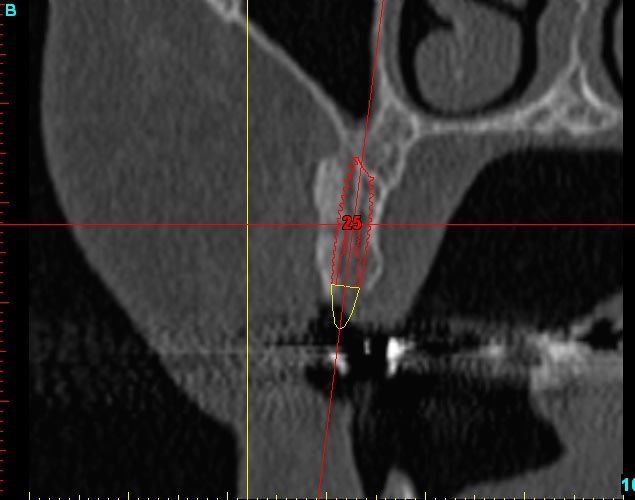

Dar12 dmdcf3 - Eugenol

Dar13 snfr77 - Eugenol

14dar tm9a6n - Eugenol

Dar14 mu6ia0 - Eugenol

15dar srylok - Eugenol

23dar fu8chl - Eugenol

Dar23 cngblb - Eugenol

24dar rfsfid - Eugenol

Dar24 scegbz - Eugenol

25dar yv2tvr - Eugenol

Dar15 gpvqe1 - Eugenol

Dar25 mrwngv - Eugenol

12dar ujxzdu - Eugenol

13dar zaa5vz - Eugenol

22dar mrs1pw - Eugenol

Darcl12.12 - Eugenol